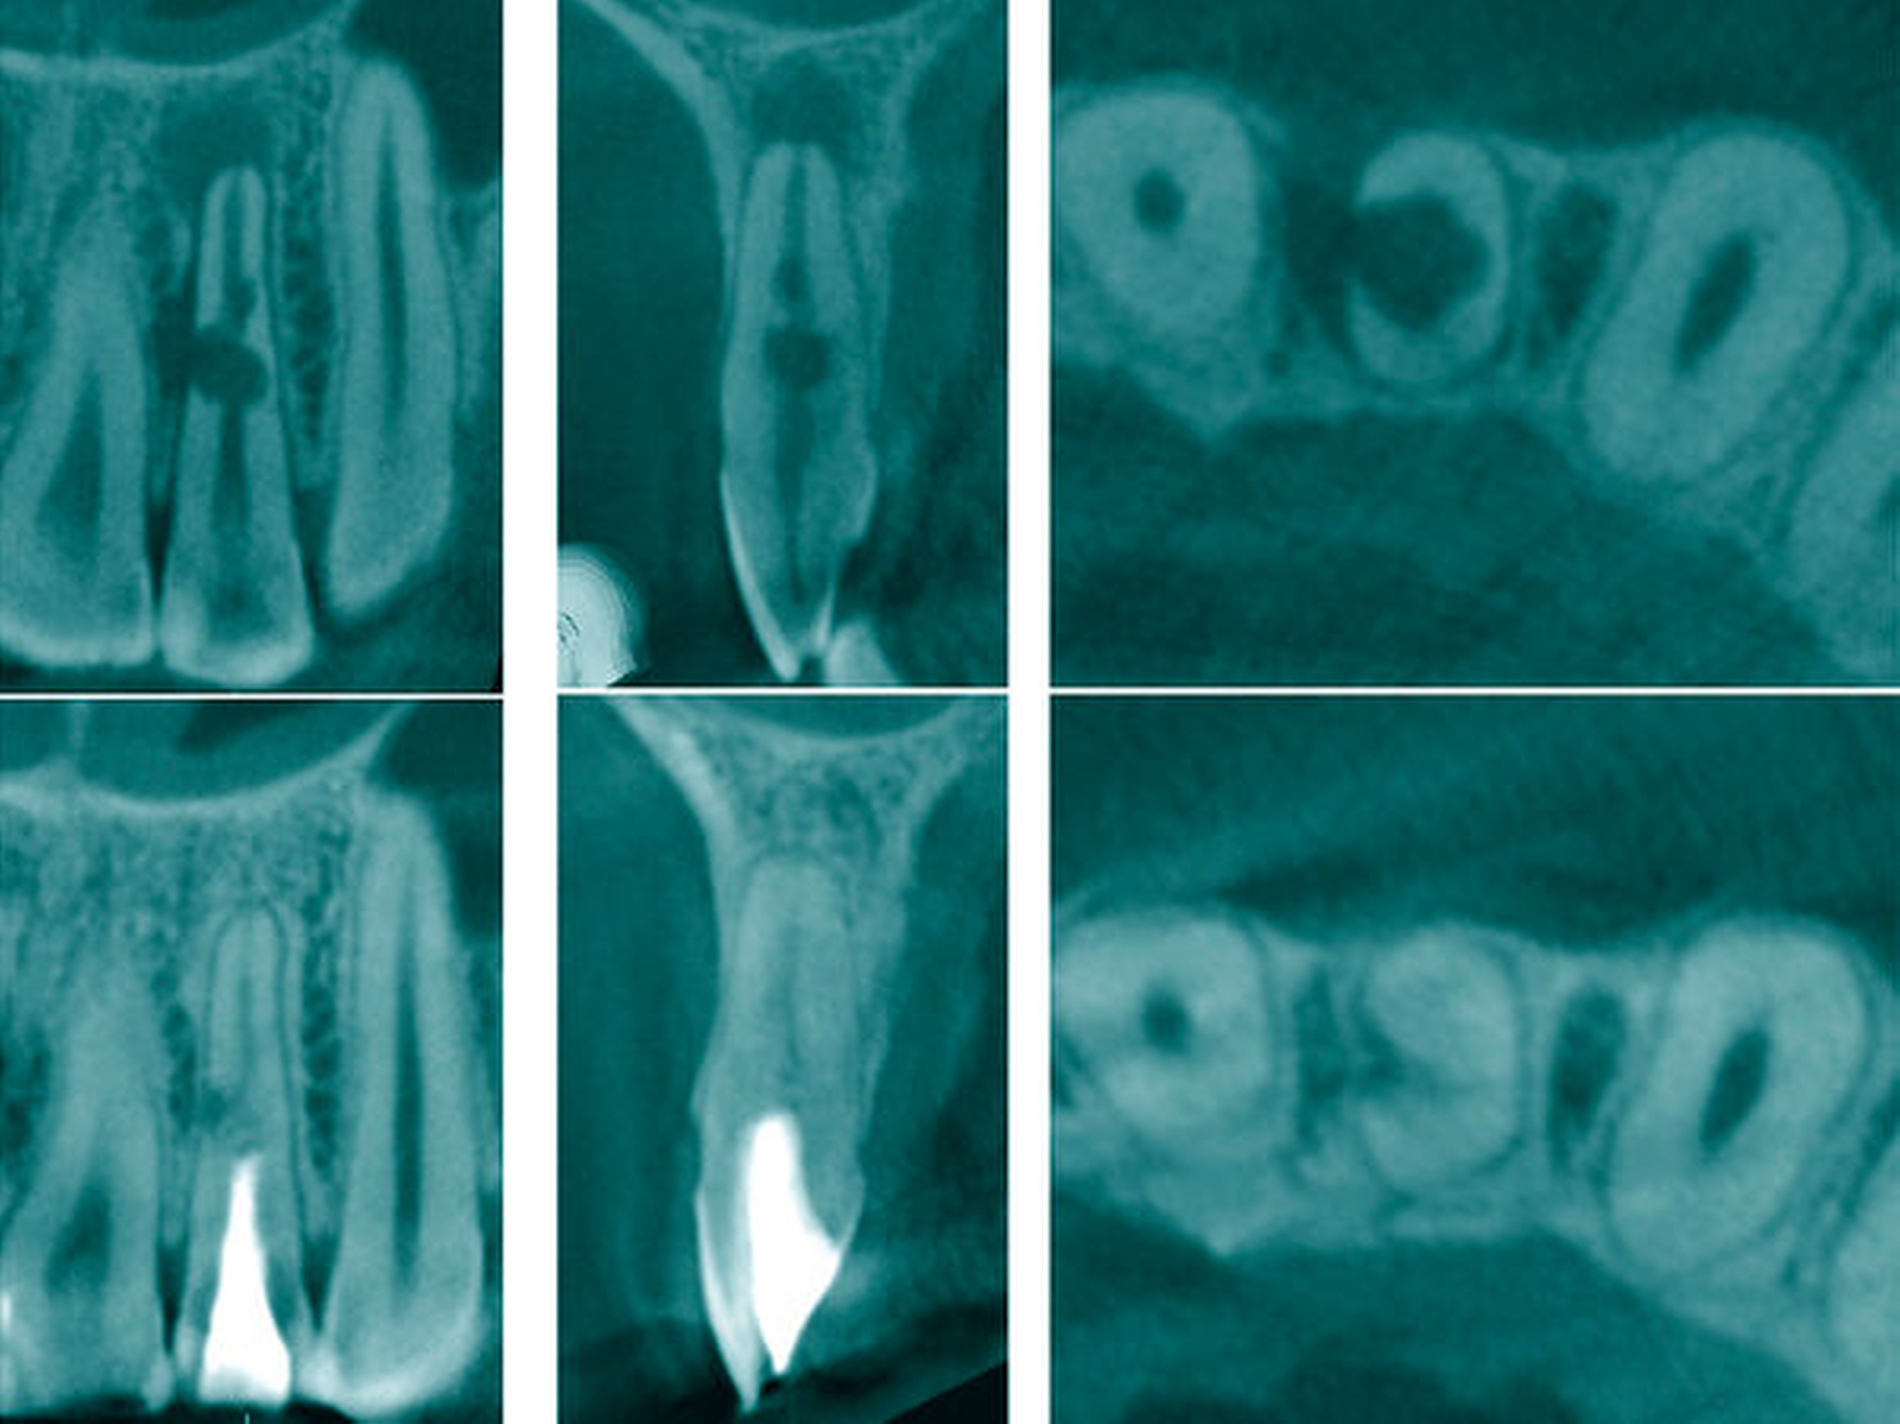

Fallbeispiel 1 (Abbildung 1)

Aufgrund einer fortbestehenden mikrobiellen Infektion wurde eine endodontische Revision am Zahn 26 erforderlich. Unter vergrößerter Sicht mit einem Dentalmikroskop ließen sich drei in Einstifttechnik gefüllte Wurzelkanäle bei achtfacher Vergrößerung darstellen. Am Boden der Pulpakammer ist das Primärdentin von dem die Pulpakammer einengenden Sekundärdentin zu differenzieren, so dass unbehandelte endodontische Hohlräume gut erkannt werden können (Abbildung 1a).

Im Verlauf des minimalinvasiven Abtrags von Sekundärdentin mit Langschaftrosenbohrern in absteigender Größe 012 bis 005 gelingt es, den zweiten Anteil des mesiobukkalen Wurzelkanalsystems (MB2) für eine mechanische Erweiterung, Reinigung und Desinfektion freizulegen (Abbildung 1b). Im Verlauf der Präparation des distobukkal teilweise gefüllten Wurzelkanals wird die Diskrepanz zwischen bisher aufbereitetem Volumen und tatsächlicher Dimension des Wurzelkanalsystems deutlich. Die Fusion der distobukkalen mit der palatinalen Wurzel hinterließ ein langgestrecktes, bandförmiges Wurzelkanalsystem mit fibrosierten und kalzifizierten nekrotischen Geweberesten (Abbildung 1c).

Unter kontinuierlicher mikroskopischer Kontrolle erfolgte die mechanische Erweiterung mit rotierenden NiTi-Instrumenten, so dass eine Desinfektion und eine vollständige thermoplastische Wurzelkanalfüllung möglich wurden (Abbildungen 1d und 1e).